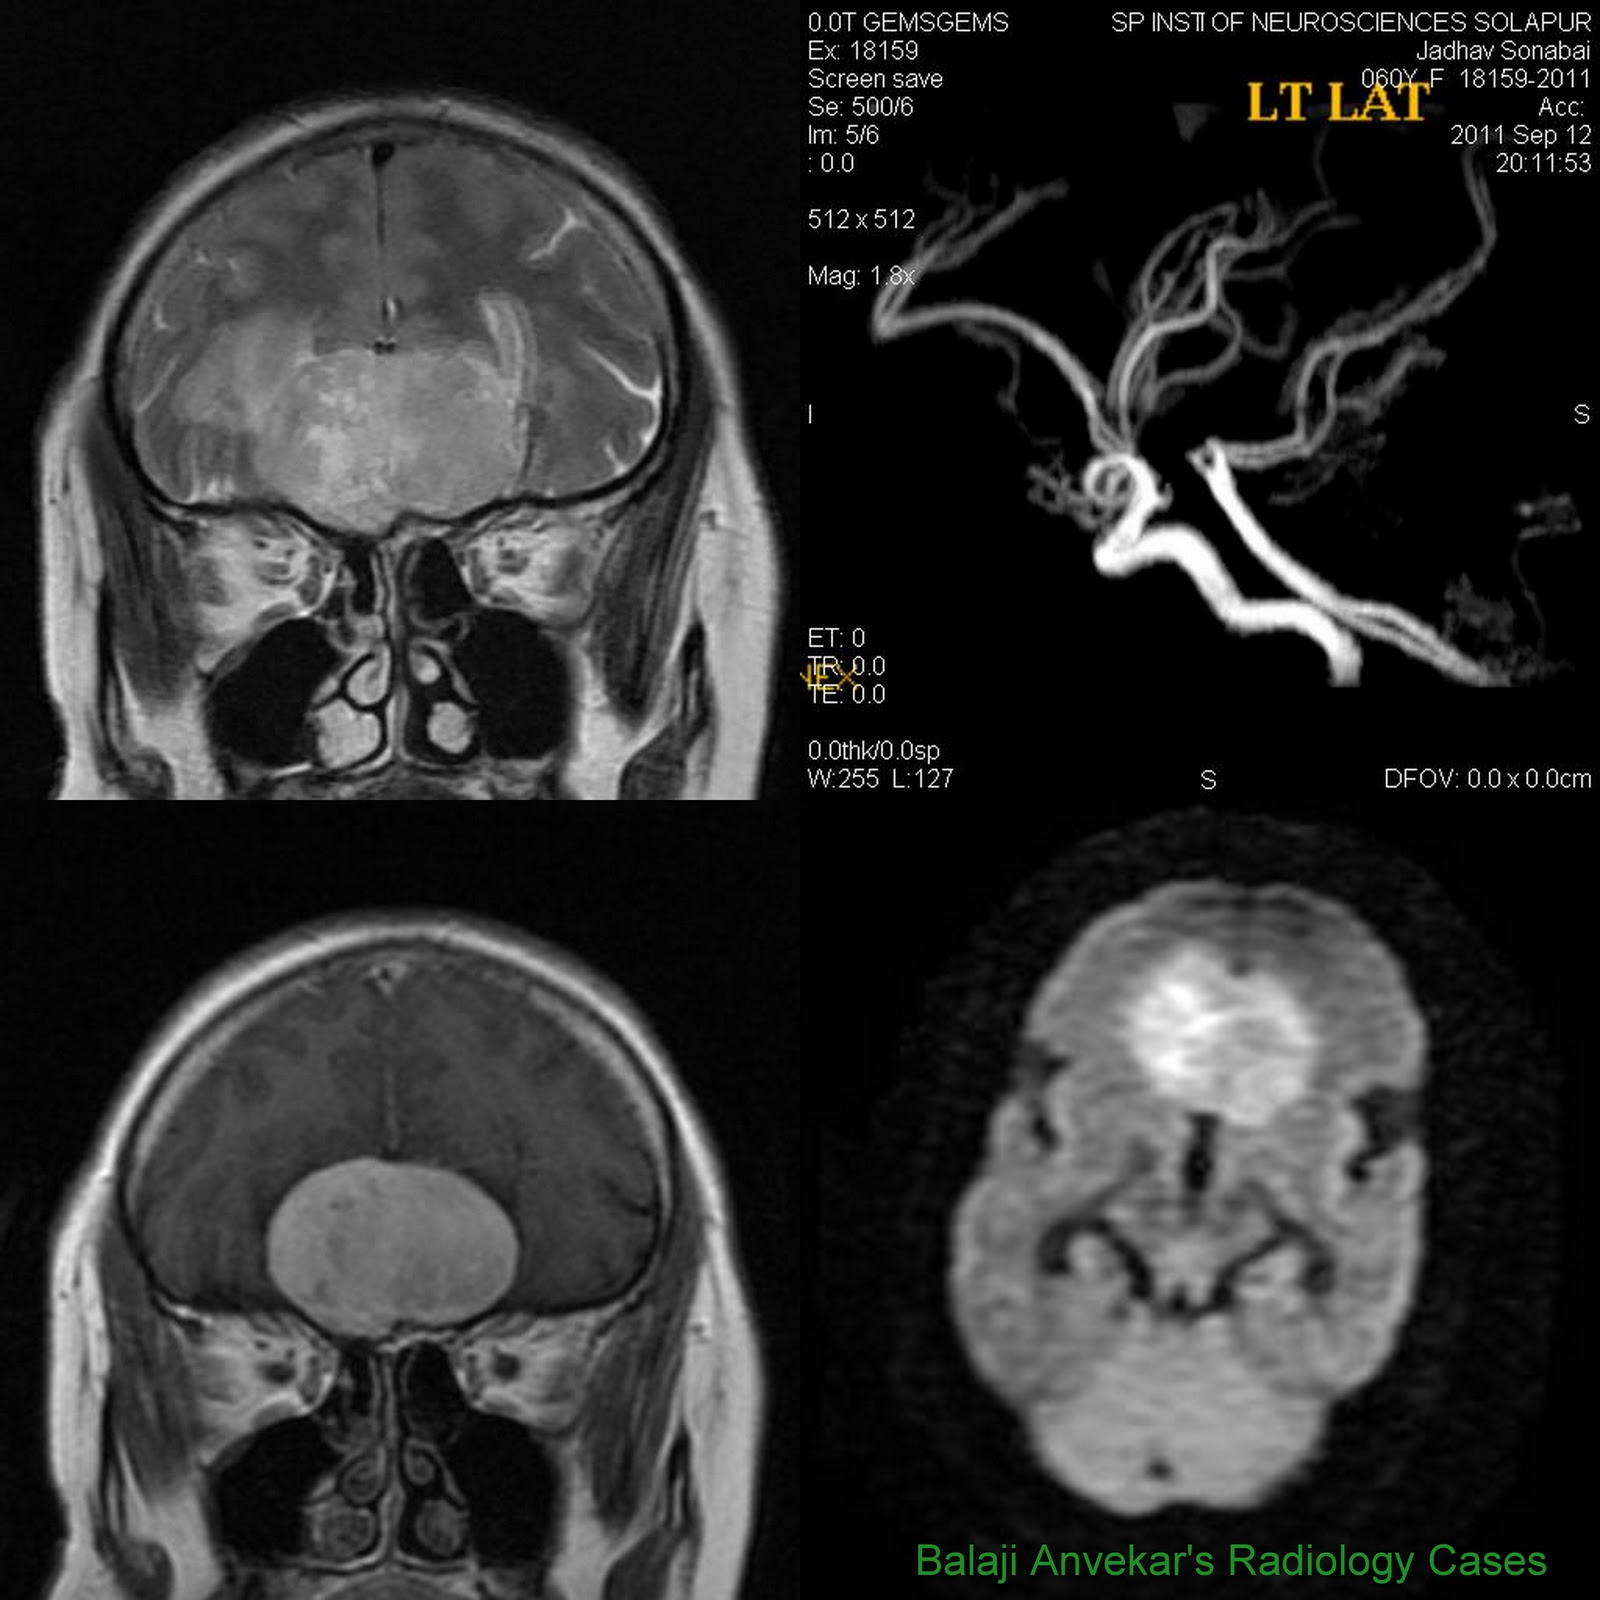

From radiocases.blogspot.com

Dr Balaji Anvekar's Neuroradiology Cases Olfactory groove Meningioma MRI What Is Olfactory Groove Meningioma Olfactory groove meningiomas are located between your brain and nose at the base of your skull. Olfactory groove meningioma forms along the nerves that run between the brain and the nose and account for around 10 percent of meningiomas. They grow near your olfactory nerve,. The mount sinai health system specializes in diagnosing and treating olfactory groove meningiomas, which are. What Is Olfactory Groove Meningioma.